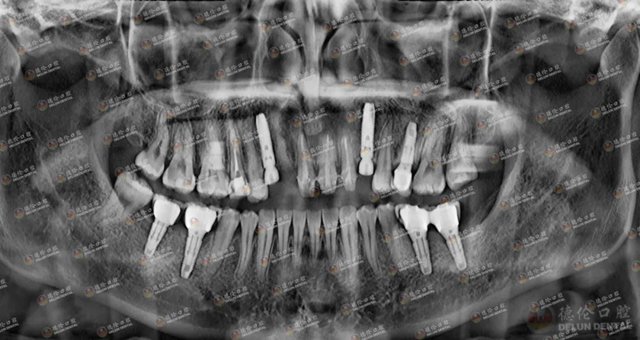

刘女士术后牙片

刘女士重获一口好牙